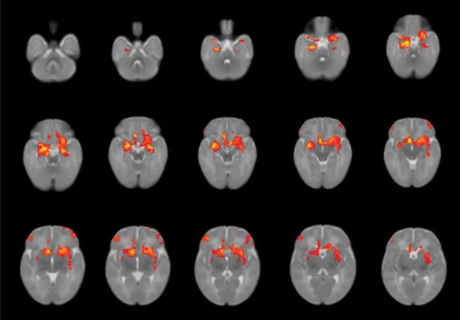

Journal: J Neurosci. 2021;41(6):1331-1339.Authors: Zhao, J., Mo, L., Bi, R., He, Z., Chen, Y., Xu, F., Xie, H., & Zhang, D. Background: The dorsolateral prefrontal cortex (DLPFC) and ventrolateral PFC (VLPFC) are both crucial structures involved in voluntary emotional regulation. However, it remains unclear whether the functions of these two cortical regions that are involved... Read more